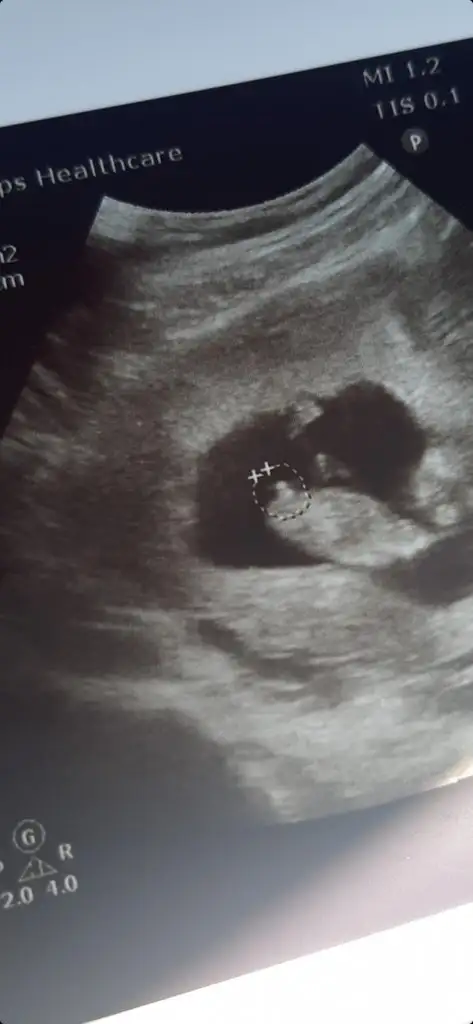

Ikra meyra bana da yorum yapar mısın cinsiyet için burada 9 haftalıktı belli olur mu bilmiyorum o haftada ama bir bakabilirsen sevinirim

Eklentiler

• IMG_20210518_165952.webp

23,5 KB · Görüntüleme: 57